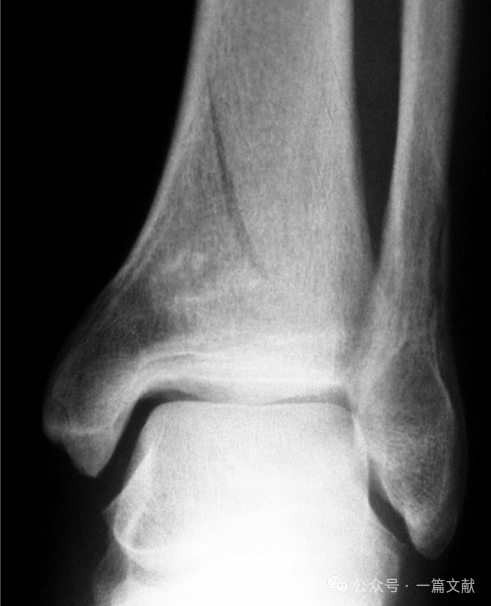

无关节面压缩,属于踝关节骨折向Pilon骨折过渡类型;

如下图: